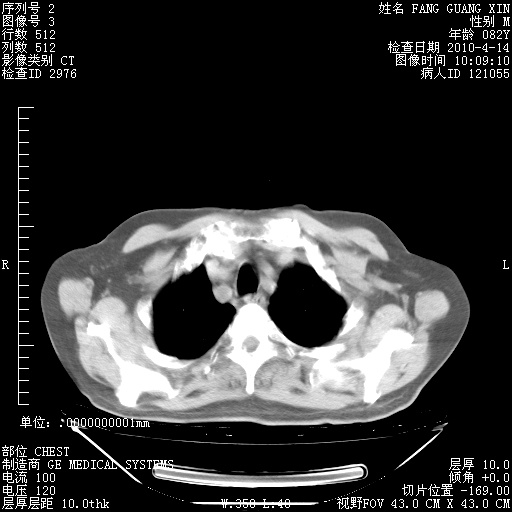

4月14日肺部CT

23.JPG

24.JPG

25.JPG

26.JPG

肺部CT平扫未见异常。